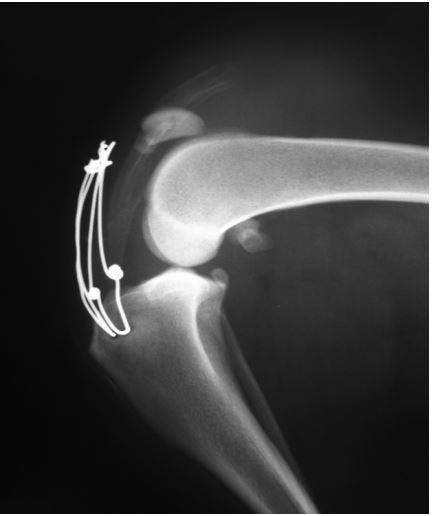

After lateral arthrotomy, the stifle was thoroughly inspected and was copiously lavaged with warm normal saline. A focal erosion of the articular cartilage was observed on the lateral side of the lateral condyle. The distal pole of the patella was fractured into several pieces that were removed (Figure 1). The straight patellar ligament was avulsed from the patella, and two loops of orthopedic wire (1.2 mm) were used for its repair. Each loop was passed through a transverse drill hole in the tibial crest and then around the patella’s lateral, proximal, and medial side (first loop) or the proximal side of the patella and on its cranial surface in figure-of-eight configurations (second loop). In the proximal side of the patella, the wires were passed through the tendon of insertion of the quadriceps muscle. Also, before the tightening of the second wire loop, several horizontal mattress sutures (propylene 0) were placed between the proximal free end of the ligament and the soft tissues in the cranial surface of the patella (Figure 2). A Penrose tube was placed in the surgical site. Postoperatively, a combination of amoxicillin plus clavulanic acid (Synulox, Zoetis, Belgium, 20 mg/kg, BID, per os, for six days) and clindamycin (Zodon, Ceva, France, 10 mg/kg, BID, per os, for 3 weeks), and also a non-steroidal anti-inflammatory drug (Rimadyl, Zoetis, England, 2 mg/kg, BID, per os, for two weeks) was administered. The activity was strictly restricted for six weeks. An Elizabethan collar was applied until suture removal. The dog was not hospitalized due to his aggressive behavior. Unfortunately, the dog did not sustain the collar, and according to the owner, two days later, the Penrose tube was “totally” removed by the dog. Also, the restriction of the dog was impossible, therefore the right hindlimb bore weight during the first 15 days. Three weeks postoperative, the dog was readmitted with persistent nonweight-bearing lameness and swelling of the right stifle. A residual piece of the Penrose tube into the joint was suspected. Plain radiographs of the right stifle revealed mildly increased synovial mass, periarticular soft tissue swelling, and position of the patella proximal to both loops of wire (Figure 4). A second surgery was performed. A large amount of sanguineous fluid was accumulated subcutaneously. Both loose wire loops were removed, but the other sutures were intact, maintaining contact between the patella and the ligament. A piece of the Penrose tube was found and removed. The joint was copiously lavaged with warm normal saline. Postoperatively, the previous antimicrobial and non-steroidal anti-inflammatory drugs were administered for a month. Restriction and physiotherapy were also advised.

Figure 4: Lateral (A) and craniocaudal (B) radiographs of the right stifle after the use of two loops of orthopedic wire for the repair of the avulsed straight patellar ligament. There is mildly increased synovial mass, periarticular soft tissue swelling and position of the patella proximal to both loops of wire.